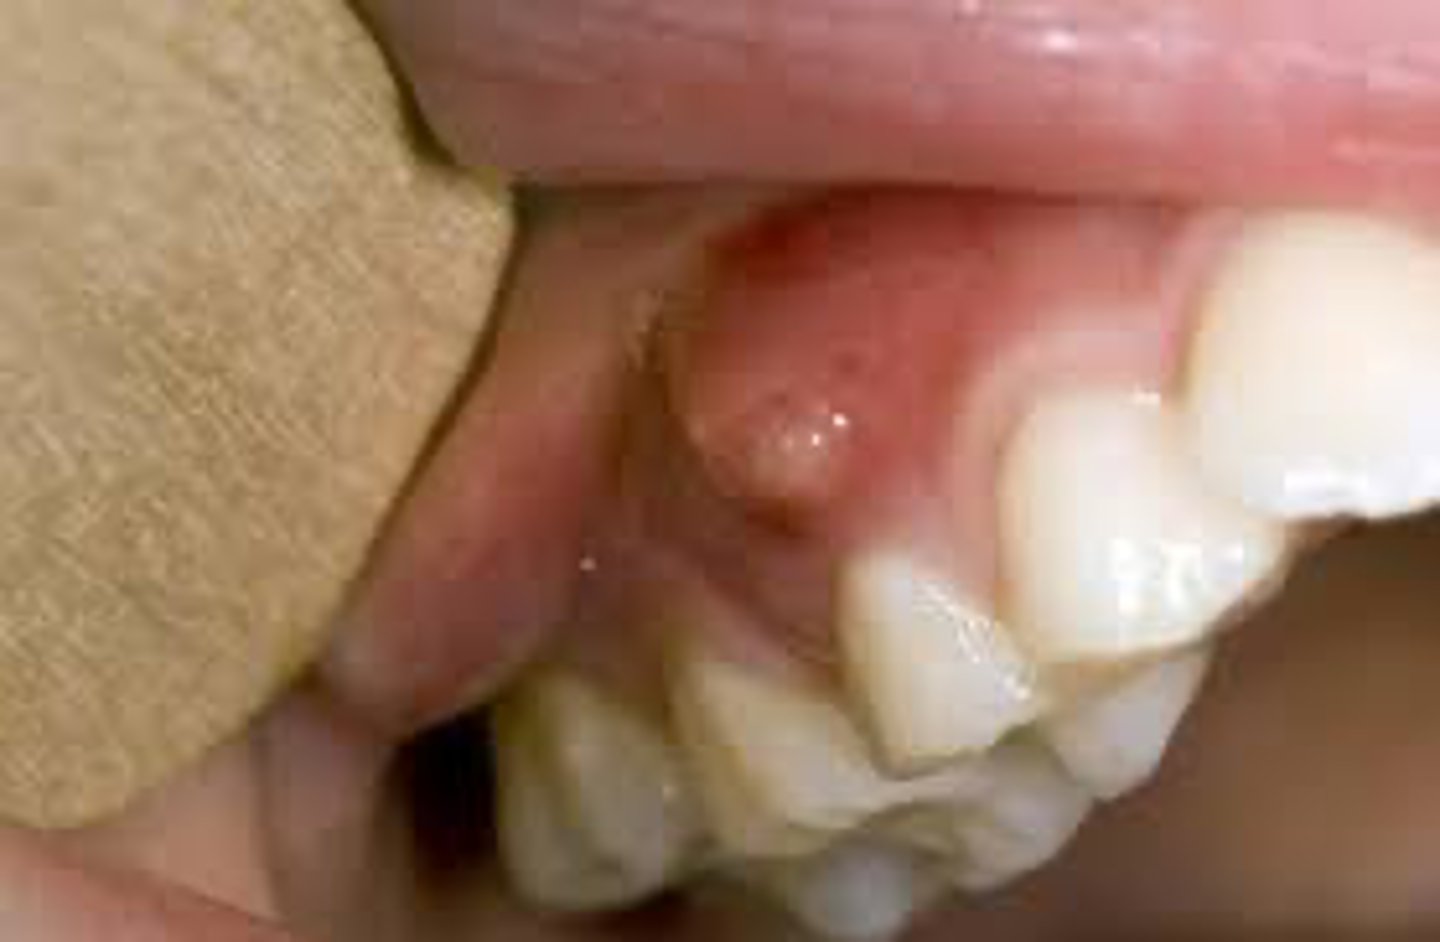

A patient presents with a small, red-yellow bump on the gingiva near a non-vital tooth. The lesion appears to contain pus.

What is the most likely diagnosis?

parulis